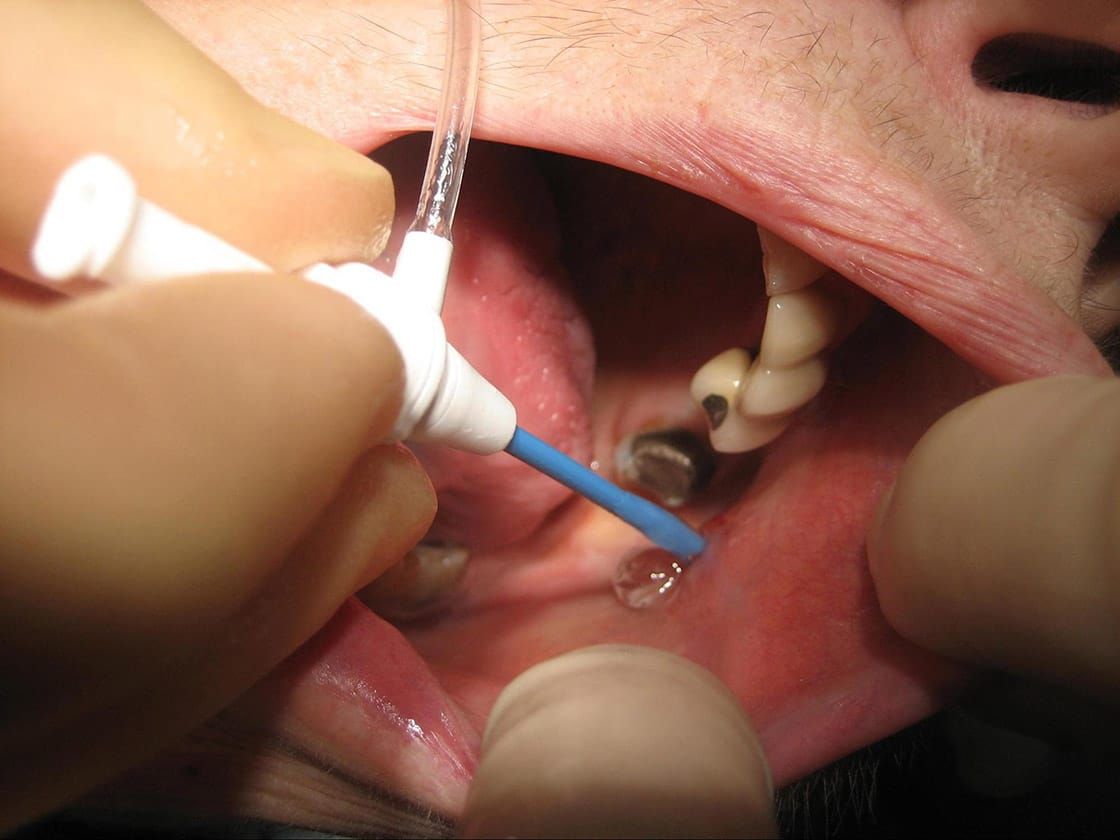

Sialendoscopy

This is a minimally invasive procedure similar to key-hole surgery, where a very small camera is inserted into the ducts through their natural openings in the mouth. The benefits of sialendoscopy are thus less swelling, pain, bleeding, infection and a faster recovery. Its completed in one visit as a day case procedure.

See below for images of stone removal from left parotid duct.